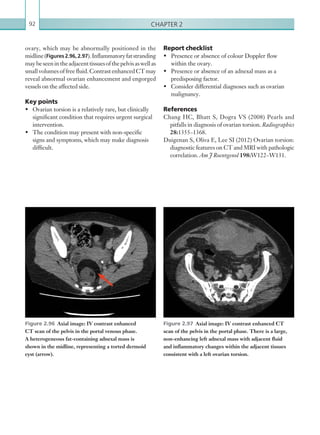

• 51.

Gastrointestinal and genitourinaryimaging 29 is more helpful in cases of occult or intermittent GI bleeding). CTA is increasingly being used as the first- line imaging modality of choice and is a useful adjunct in cases where endoscopy has failed to identify a source of bleeding. The sensitivity of CT decreases if bleeding is intermittent and timing the scan with the clinical signs of active bleeding is essential. Utilising triple- phase CTA (unenhanced, arterial and delayed phases) increases sensitivity and specificity when compared with using a single phase only. Oral contrast may mask the potential site of bleeding and should therefore be omitted. It is also important to consider whether the patient has had any recent oral contrast examinations, since this can also lead to a false-positive result. Barium enemas are of particular importance, since the oral contrast can remain in diverticulae for months or even years.Catheterangiographyisinvasiveandisnowadays lesssensitivethanCTA;assuchitisgenerallyperformed once CTA has identified a bleeding point, with an aim to embolisation and treatment. (See Table 2.3.) Radiological findings Computed tomography The GI tract should be scrutinised systematically, with careful attention being paid to the locations that are common sources of bleeding (stomach, duodenum and colon). The focus of acute GI bleeding is located by identifying high attenuation material (90 Hu) within the bowel lumen on the arterial phased scan, which represents active extravasation of IV contrast. ACUTE GASTROINTESTINAL BLEEDING Acute gastrointestinal (GI) bleeding is a medical and surgical emergency, with an associated mortality of up to 40% (Walsh et al., 1993). GI bleeding has many causes (Table 2.2) and can be divided into upper and lower tract bleeding, according to its location in relation to the ligament of Treitz. Upper tract bleeding is more common than lower tract bleeding, comprising approximately 75% of cases (Ernst et al., 1999). Symptoms such as haematemesis and melaena usually indicateanuppertractsource,whereasfreshperrectum bleeding usually signifies bleeding from the lower GI tract. Profound bleeding can result in haemodynamic instability and therefore urgent localisation of the source is vital. Endoscopy has traditionally been considered the first-line investigation for suspected GI bleeding, especially in cases of suspected upper tract bleeding. Limitations of endoscopy include an inability to visualise the upper tract distal to the fourth part of theduodenumanddifficultyinvisualisingbleedingfoci because of profound intraluminal haemorrhage. With the increasing sensitivity of CT and ease of access, radiological investigations are increasingly being considered as the first-line investigation. Radiological investigations Radiological investigations that play a part in the management of GI bleeding include CTA, catheter angiography and radionucleotide imaging (the latter UPPER LOWER Mallory–Weiss tear Angiodysplasia Oesophageal varices Diverticulitis Gastric/duodenal ulcer Colitis Gastritis Malignancy Malignancy Table 2.2  Causes of gastrointestinal bleeding. MODALITY PROTOCOL CT Unenhanced. No oral contrast. Scan from above diaphragm to femoral head level. Aortic angiogram: 100 ml IV contrast via 18G cannula, 4 ml/sec. Bolus track centred on mid-abdominal aorta. No oral contrast. Scan from above diaphragm to femoral head level. Delayed phase. IV contrast as above, scan at 120 seconds after start of contrast injection. No oral contrast. Scan from above diaphragm to femoral head level. Table 2.3 Acute gastrointestinal bleeding. Imaging protocol. K22247_C002.indd 29 16/05/15 3:07 AM

• 52.

Chapter 230 This isusually more apparent and accumulates on the delayed phase (Figures 2.7, 2.8). It is vital to scrutinise the unenhanced phase to assess for pre- existing foci of high attenuation within the bowel lumen that may lead to false positives; these can include ingested tablets, foreign bodies and suture material. Previous imaging should also be reviewed in this regard. Cone beam artefact is another common false positive, occurring at interfaces between fluid and air within the bowel. Bleeding in the distal oesophagus may be secondary to oesophageal varices, a complication of portal hypertension. These may be visualised as dilated, • Splenomegaly. • Ascites. • Varices: splenic/oesophageal. • Underlying cause (i.e. liver cirrhosis with atrophy and nodular/irregular contour). • Contrast enhancement of para-umbilical vein. Table 2.4 Computed tomographic signs of portal hypertension. Figure 2.7  Axial image: contrast enhanced CT scan of the abdomen in the arterial phase. Hyperdense material can be seen in a dependent position within the lumen of the ascending colon (arrow), consistent with an acute, arterial haemorrhage. Figure 2.8  Axial image: contrast enhanced CT scan of the abdomen in the delayed phase. On delayed imaging, further contrast has accumulated within the lumen of the ascending colon as a result of continued, active haemorrhage at this site. serpiginous enhancing vessels in the region of the distal oesophagus. Findings suggestive of liver cirrhosis and portal hypertension, such as an irregular liver outline and splenic enlargement, should prompt the search for oesophageal varices (Table 2.4; Figures 2.9, 2.10). IfGIbleedingisidentified,itisimportantto consider anunderlyingcause.Muralthickeningcanbemalignant, inflammatory, ischaemic or infective in nature, all of whichcanbecomplicatedbybleeding.Itisalsoimportant to appreciate that GI bleeding is often intermittent and it is not uncommon for CTA to be normal, even in haemodynamically compromised patients. K22247_C002.indd 30 16/05/15 3:07 AM

• 53.

Gastrointestinal and genitourinaryimaging 31 Figure 2.9a, b  Axial and coronal images: unenhanced CT scans of the abdomen. A transjugular intrahepatic portosystemic shunt (arrow) and coiled oesophageal varices are shown. Figures 2.10a–c  Axial images: unenhanced, ­arterial and delayed phase CT scans of the abdomen. This sequence of images demonstrates a contrast blush on the arterial phase within the stomach (arrow). No ­corresponding density is seen on the unenhanced scan. Findings are in keeping with acute gastric bleeding. The spleen is enlarged, ­suggestive of underlying portal hypertension. (a) ( b) (c) ( b)(a) K22247_C002.indd 31 16/05/15 3:07 AM